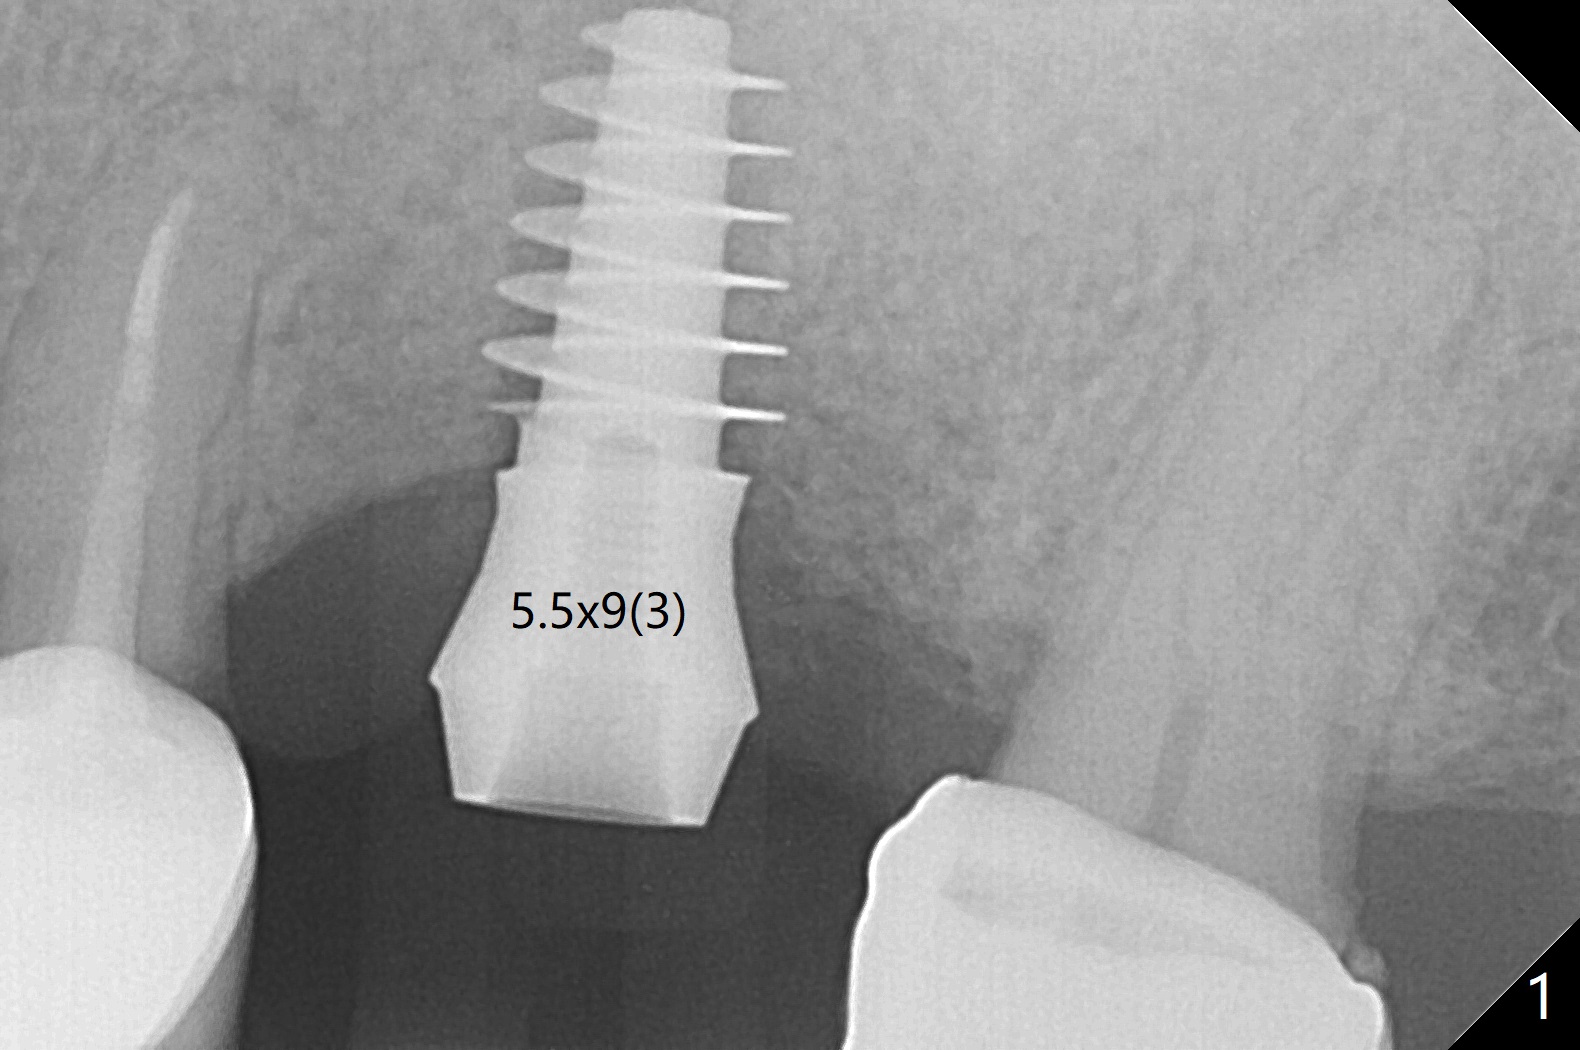

After 4.5x11.5 mm drill (10.5 mm offset) and 5.0 mm tap with guide at #14, the depth of the gingiva is measured 3 mm. A 5.5x9(3) mm Magicore cannot enter the green sleeve and is placed free hand (Fig.1). The margin is slight subgingival mesiodistal. With 3-4 turns, the buccal margin is slightly subgingival, while the palatal one slightly supragingival (Fig.2). The length of the implant could be 11 mm, considering the apical space (double arrows). To prevent periimplantitis, what is the appropriate placement depth coronally? Where does Titanium end? Dr. Wang thinks that the placement level is right. Probably due to underprep, the mesial crestal bone appears to have been resorbed 7 months postop (Fig.3 ^, as compared to Fig.1). The gingiva is healthy. A 4.3x5 mm solid abutment is torqued 20 Ncm for impression. The guide allows the implant to be placed lingual because of buccal concavity (Fig.4), but the coronal end of the solid abutment in the center for restoration (Fig.5 A). The crown is seated partially on the Magicore (M). The temp bond cemented crown is off 8 months post cementation (Fig.6). The bone density increases especially mesial.